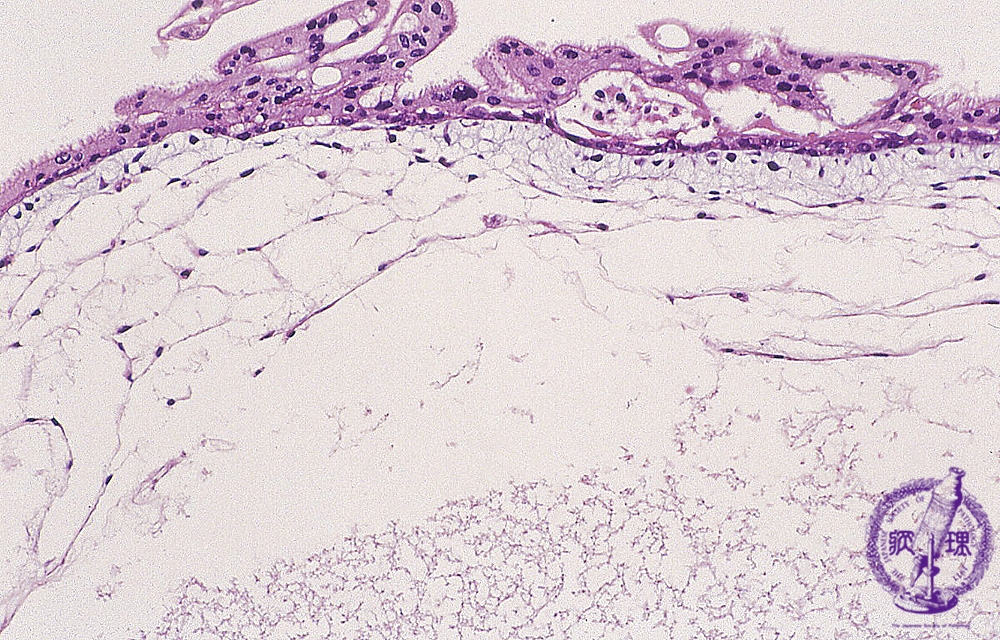

胞状奇胎(全、部分)ミクロ像(HE中拡大)

ミクロ像(HE中拡大):水腫状に腫大した絨毛で、間質の血管は認められない。絨毛上皮細胞の増殖が軽度認められる。